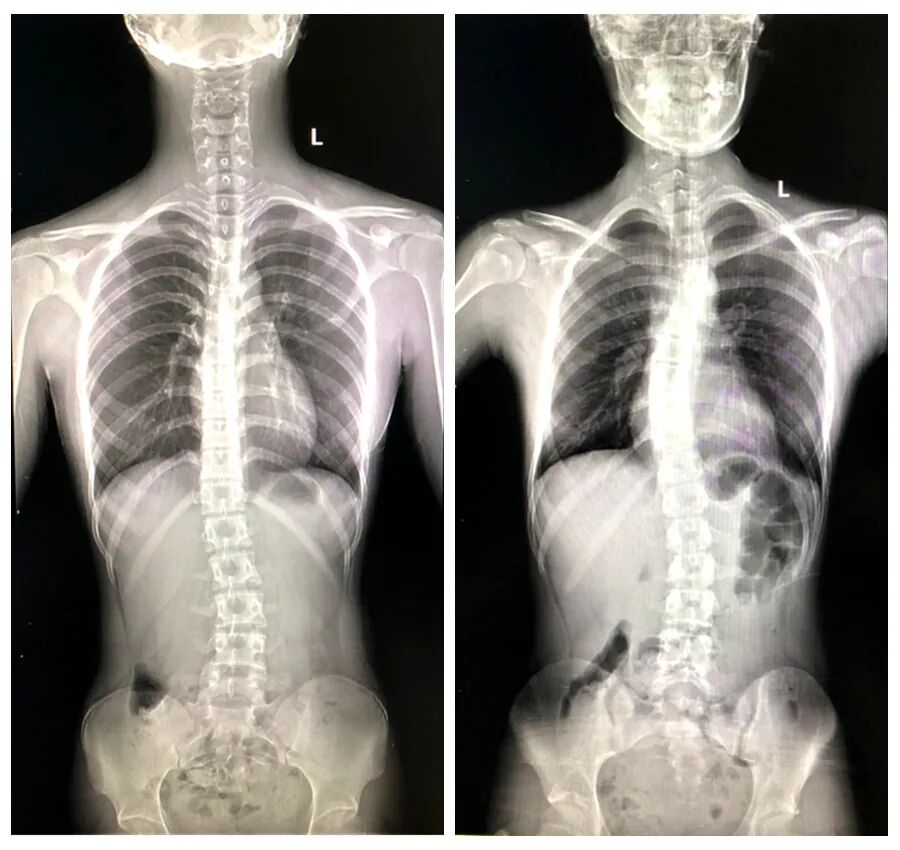

▲多功能DR脊柱全长片,脊柱侧弯畸形

脊柱侧弯是青少年常见骨骼问题,尤其在生长发育期,畸形进展风险高。不仅影响体态,更可能压迫内脏,导致功能障碍。全脊柱X线摄影是诊断脊柱侧弯的金标准,可清晰显示脊柱全长曲线,为矫形治疗提供精准依据。

多功能动态平板DR:全脊柱摄影的利器